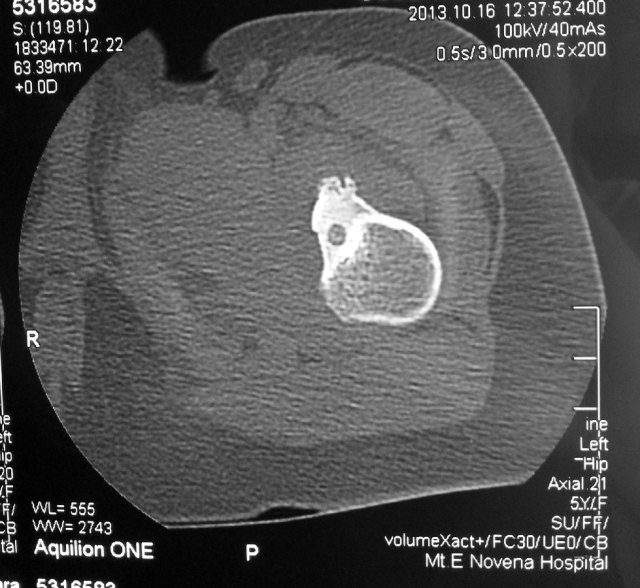

This girl was crying in pain by the time the CT-scans were done. It was obvious that something was wrong. The CT-scan confirmed the presence of an osteoid osteoma of the lesser trochanter of her left hip with pain over her left thigh.

She underwent percutaneous radiofrequency ablation of the tumour under general anaesthesia.

This procedure is done under CT-fluoroscopic guidance.

A 16F needle is inserted through the skin and advanced in a safe zone into the bone of the lesser trochanter under CT-guidance.

The radiofrequency probe is then inserted into the bony tumour.

Correct placement of the radiofrequency probe into the bony tumour lesion is confirmed on CT-scan.

Heat energy is generated by this radiofrequency machine. About 6 minutes worth of energy at 90 degreec Celcius is used to burn the lesion.